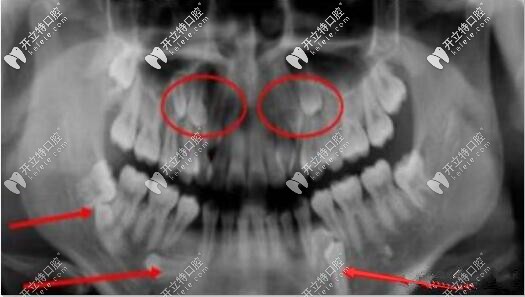

多生牙全景片

發(fā)病原因:多生牙病因不明,具有常染色體顯性遺傳性,可能來源于恒牙蕾自身分裂。

多生牙一般分萌出和不萌出埋伏阻生兩種,有些牙齒還倒長。

多生牙在任何牙位都可能發(fā)生多生牙,但常見的是上頜“正中多生牙”,其后,依次排為上頜第四磨牙等。